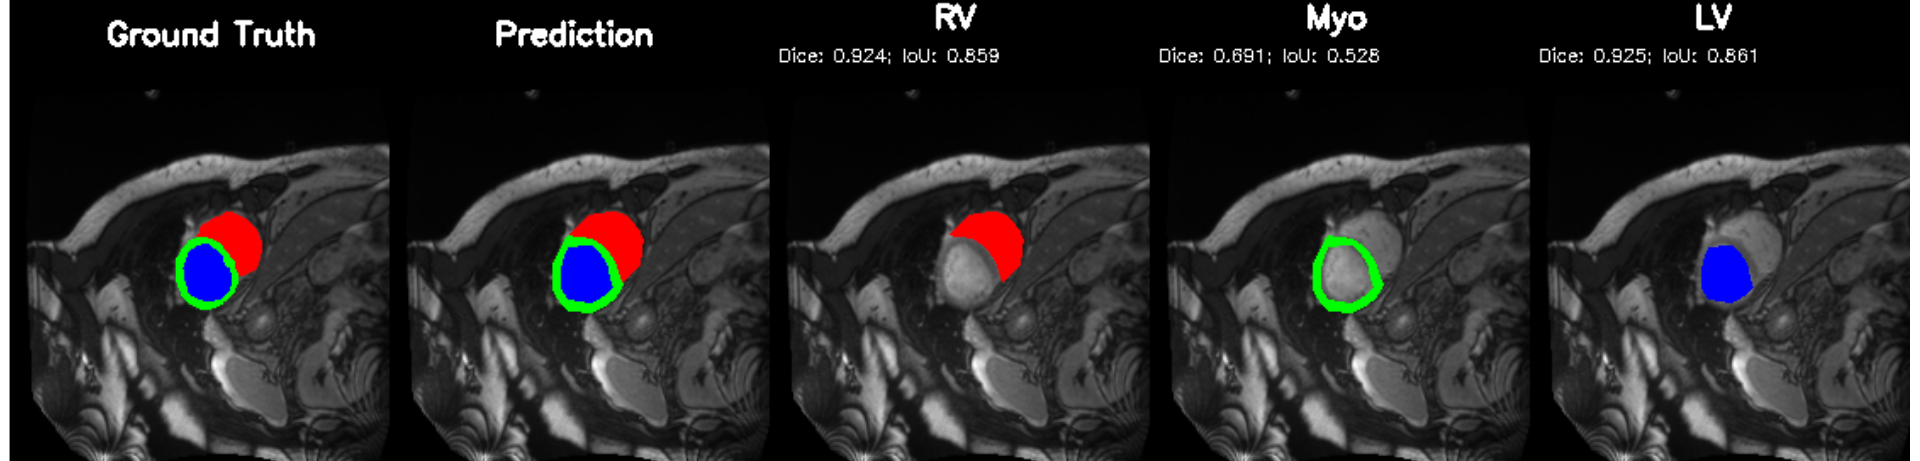

5.2 M&Ms Cine-MRI Generalization

Figure 8 illustrates segmentation outputs on the M&Ms (Multi-Centre, Multi-Vendor) cine-MRI dataset, which exhibits both contrast variation and vendor–specific acquisition differences compared to ACDC. The model retains consistent ventricular geometry, recovering LV and Myocardium structure without retraining, mirroring the zero-shot Dice performance of 74.8% (Table 11). Boundary thickness remains physiologically accurate, with only minor degradation in the right ventricle, an expected behaviour under cross-domain shifts and also reflected quantitatively in the ablation-driven robustness improvements from normalization and loss design. These results demonstrate that PULSE does not overfit to a single scanner distribution but instead transfers cardiac structure priors across unseen clinical environments.